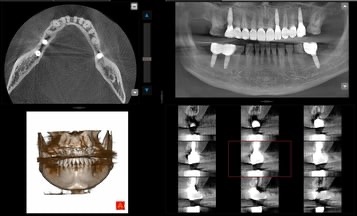

Înainte de orice intervenție, pacienții beneficiază de radiologie digitală realizată direct în clinică, o etapă esențială pentru a detecta problemele ce nu sunt vizibile cu ochiul liber.

Se analizează în detaliu mușcătura cu ajutorul scanării digitale, iar toate aceste informații sunt transmise laboratorului de tehnică dentară pentru a crea o lucrare personalizată și precisă.